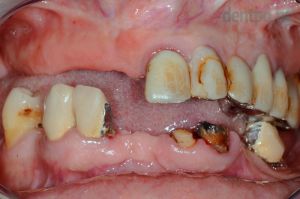

62 éves nő páciensünk előrehaladott fogszuvasodásokkal és csontpusztulással kereste fel rendelőnket. Sajnos ezek miatt egyik foga sem volt megtartható, így implantátumokra rögzített alsó körhíddal, ill. felső kivehető fogsorral pótoltuk hiányzó fogait. A fogeltávolításokat követően 6 héttel történt az implantáció és a csontpótlás. 6 hónap gyógyulást követően készültek el a végleges fogpótlások, azonban a csontosodás ideje alatt az implantátumokat azonnal terheltük, így a páciens rögtön a műtét után ideiglenes fogpótlásokkal távozhatott.

1) Kiindulási helyzet

2) Gyógyult implantátumok

3) Elkészült hídpótlás

4) Esztétikus mosoly